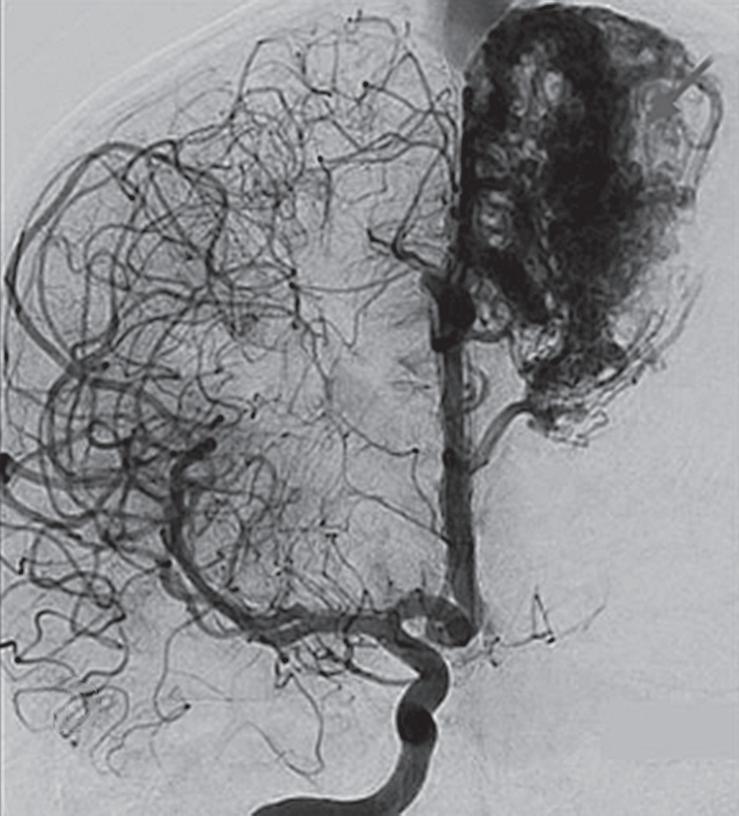

Fig. 1-16. RNM encéfalo T1 com contraste: (a) Coronal e (b) axial demonstrando MAV grau 4 frontoparietal esquerda. (c,d) Arteriografia cerebral AP mostrando a irrigação pelos ramos da cerebral anterior e média esquerda, além da cerebral anterior direita, com drenagem superficial para o seio sagital superior. Seta azul apontando para o nidus da MAV.

Fig. 1-17. RNM encéfalo T1 com contraste (a) axial e (b) T2 sagital demonstrando MAV grau 5 profunda temporoinsular esquerda com extensão nos núcleos da base. (c,d) Arteriografia cerebral,demonstrando a drenagem venosa profunda para veia cerebral interna (seta azul) com sinais de hipertensão.